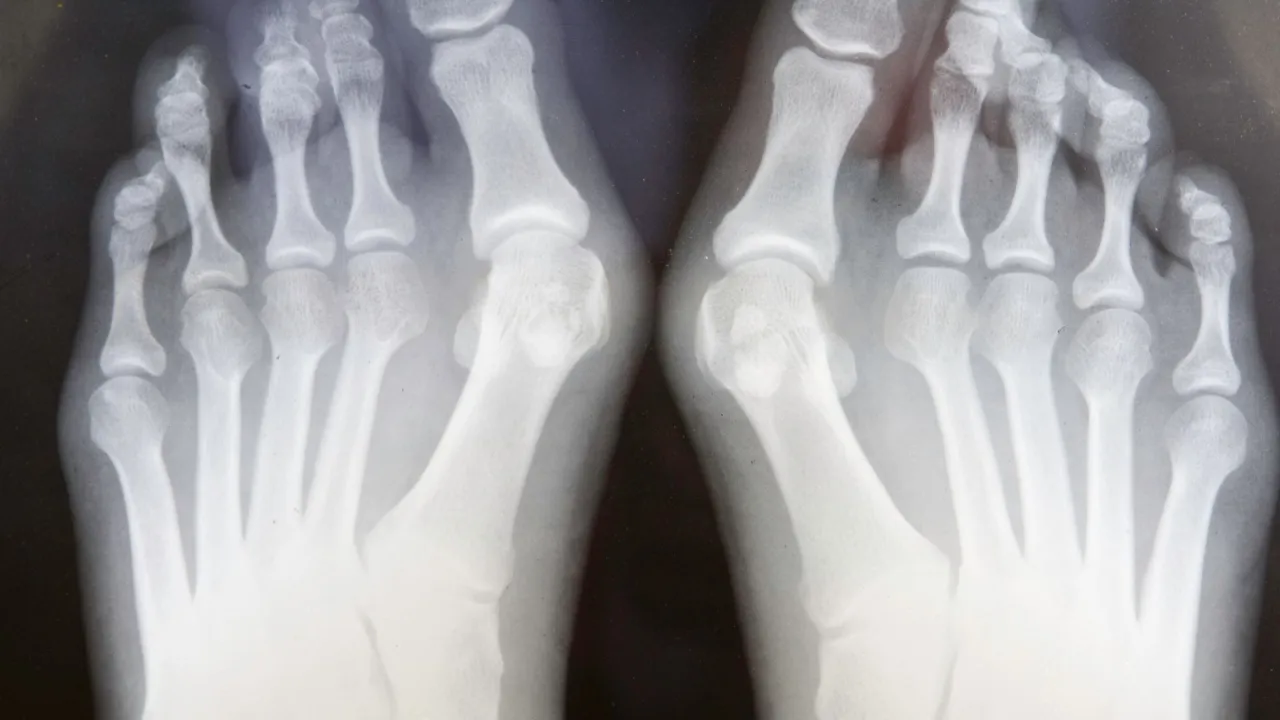

- Diagnostyka opiera się na badaniu fizykalnym i kluczowym zdjęciu RTG stóp w obciążeniu.

Badanie radiologiczne, czyli zdjęcie rentgenowskie stóp wykonane w pozycji stojącej (w obciążeniu), jest kluczowe dla prawidłowej oceny stopnia zaawansowania haluksów. Pozwala ono na dokładne zmierzenie kątów deformacji, takich jak kąt koślawości palucha (HVA Hallux Valgus Angle) oraz kąt międzypalcowy (IMA Intermetatarsal Angle). Te pomiary są niezbędne do określenia rodzaju i rozległości schorzenia, co z kolei umożliwia dobór najodpowiedniejszej metody leczenia, zarówno zachowawczego, jak i operacyjnego.